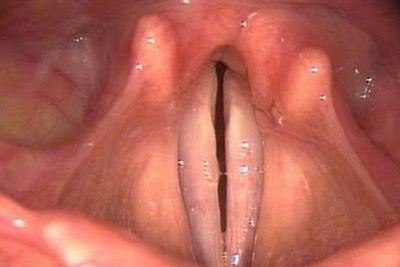

Например, сонливость может быть симптомом, в то время как расширенные зрачки могут быть знаком.Голосовые складки состоят из двух связок мышцы, расположенной в трахее (вход в трахею). Когда мы делаем произнесение (произведите звук изо рта), две связки мышечной ткани трогают друг друга и вибрируют. Когда мы не произносим звуки, голосовые складки находятся в открытом, расслабленном положении, позволяя воздуху течь свободно в нашу трахею – разрешение нам дышать.

Следующие диагностические анализы могут также быть заказаны:Эндоскопия – длинная, тонкая, гибкая труба (эндоскоп) используется, чтобы посмотреть на голосовые складки. Может использоваться специальное устройство с маленькой камерой в конце (videostrobolaryngoscopy). Доктор может получить хороший взгляд на голосовые складки на мониторе.